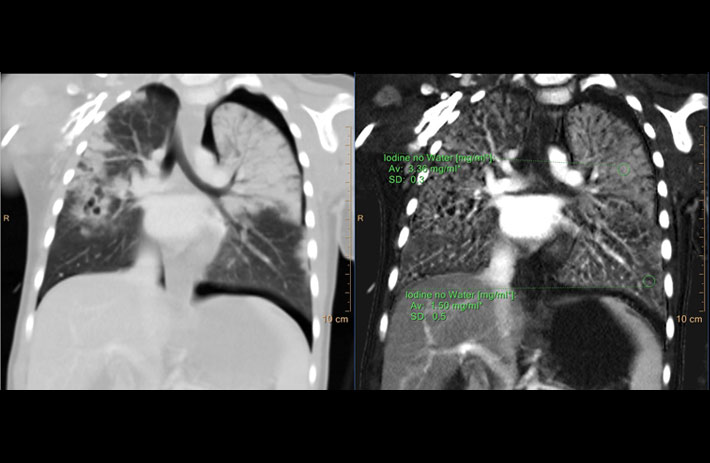

Mit dem Spektral-Detektor-CT werden Spektraldaten automatisch bei jedem Scan erfasst. Die Informationen stehen jederzeit auf der Scankonsole, der CT-Workstation sowie an jedem PACS-Arbeitsplatz zur Verfügung, sodass es nicht notwendig ist, den Patienten erneut zu scannen, bspw. wenn initial zufällige Anomalien festgestellt wurden. Dadurch profitieren Anwender durch eine höhere Diagnosesicherheit und weniger Nachuntersuchungen auf anderen bildgebenden Systemen. Unsere Fallsammlung zeigt, welchen klinischen Mehrwert der Spektral-Detektor-CT in unterschiedlichsten Anwendungsbereichen in der klinischen Routine bringt. Jede Woche gehen neue Fälle live.